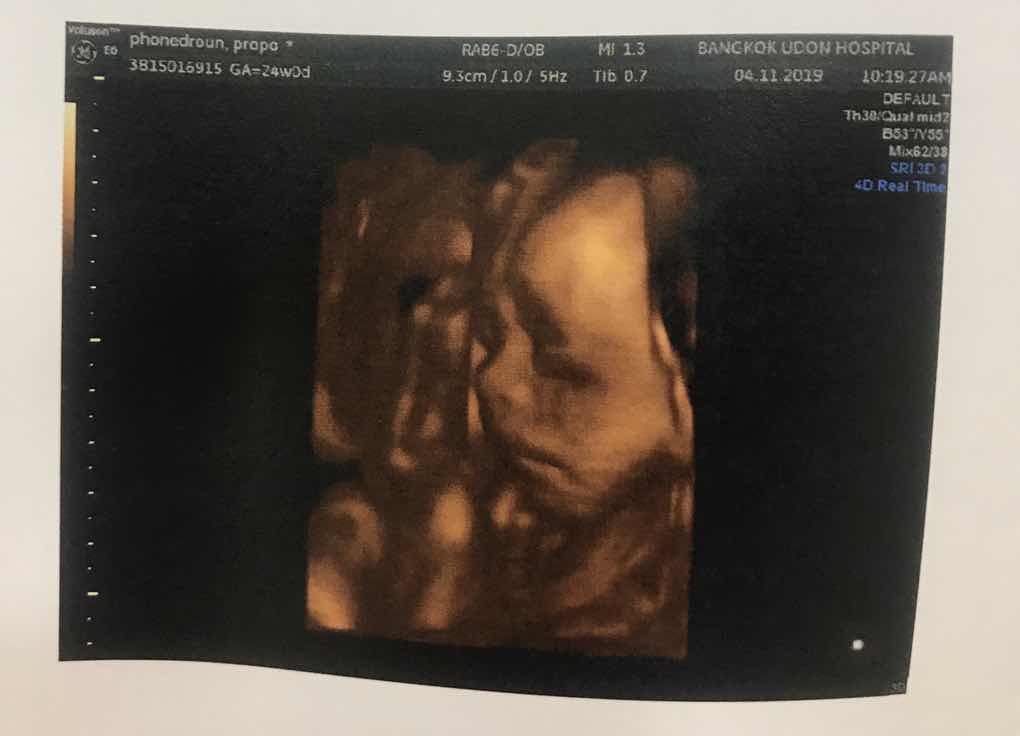

ชัดไม๊ค่ะ ❤

5 เดือน แร้ววววค่า

ตั้งแต่เริ่มท้องมาซาวด์ทุกเดือน ก็ชัดมาตลอด จนมาเข้าเดือนที่ 7 และเดือนที่ 8 แผ่นรกดันมาบังด้านหน้า ทำให้ดูหน้าไม่ชัดเจน รอลุ้นซาวด์ครั้งหน้า 8 เดือนกับ 3 สัปดาห์ ว่าจะเห็นหน้าน้องชัดขึ้นใหม รึจะได้ลุ้นความหล่อตอนคลอดเลยก็ไม่รู้ #รูปซาวด์ตอน 6 เดือน ชัดสุดแล้ว 🥰

ชัดมากค่ะ ซาวแบบ 4 มิติหรอคะ ซาวที่ไหนคะ

ไช่ค่ะ 4 มิติค่ะ 😘